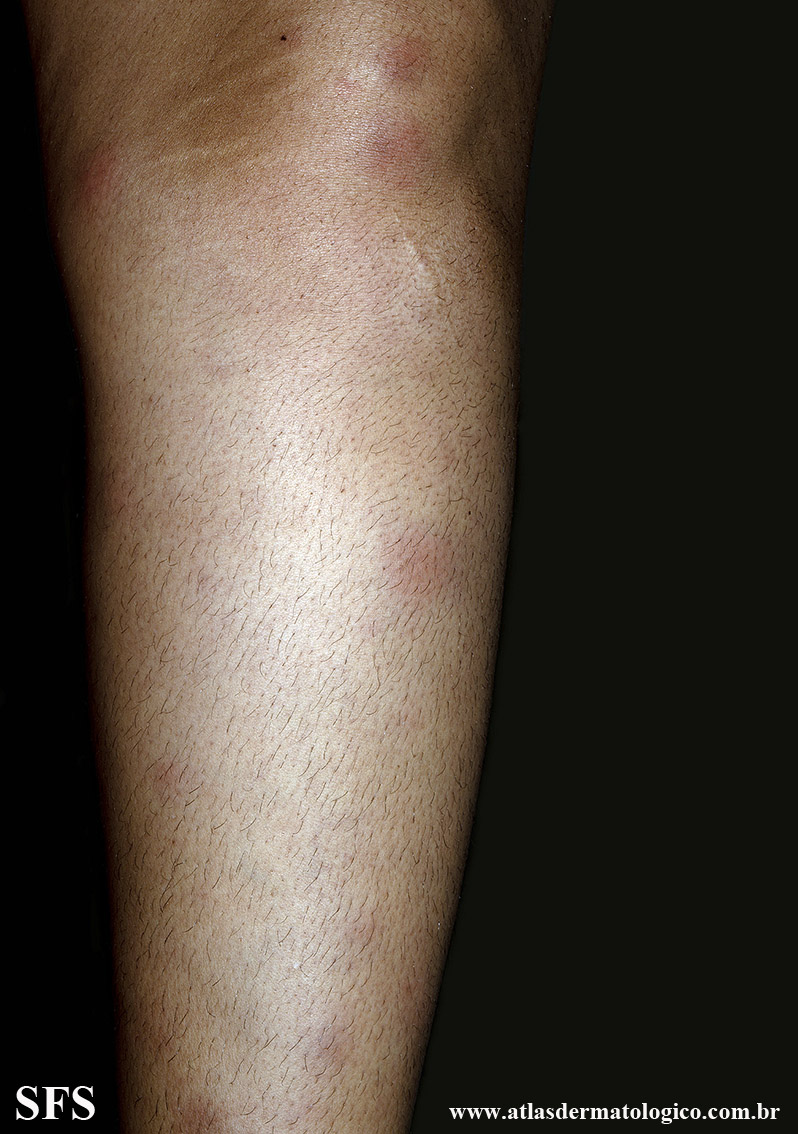

erythema nodosum